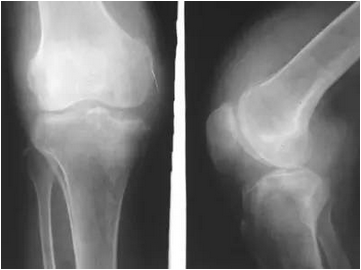

宜昌男子暴走3万步撕裂半月板!

在朋友圈拼步数,一天走了3万步,52岁的陈先生怎么也没想到右膝会因此疼痛难忍。前不久,记者从宜昌市一医院康复科获悉,经诊断,陈先生是运动过度导致膝关节积液、半月板撕裂。“患者体重较重,加上运动过量,已引起膝关节损伤,造成膝关节积液、半月板撕裂。目前正进行康复治疗,如恢复不佳就只能手术了。”康复科主任黄肖群表示,因拼步数引起的膝关节损伤在临床上并不少见,多是运动过量引起急性损伤。